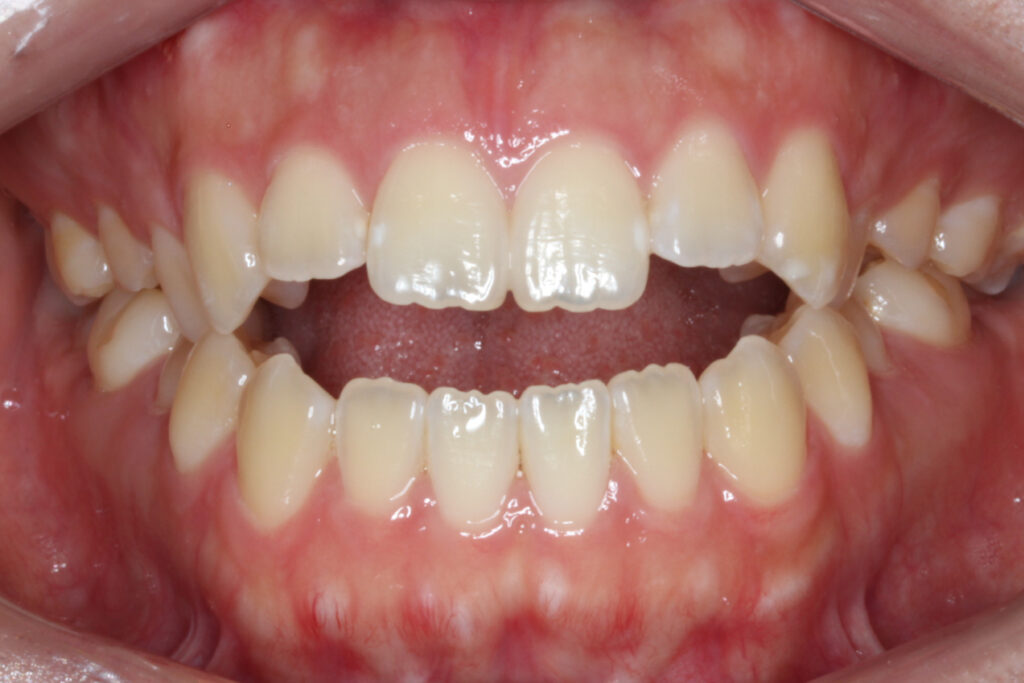

開咬(case 5)

滑舌が悪い、前歯でものが噛めない(インビザライン)

滑舌が悪いことと、前歯でものが噛めないとのことで矯正治療を行いました。

噛み合わせた際、上下顎の前歯が垂直的に被さらず空間ができている、「開咬」という歯並びの状態になっています。

Before